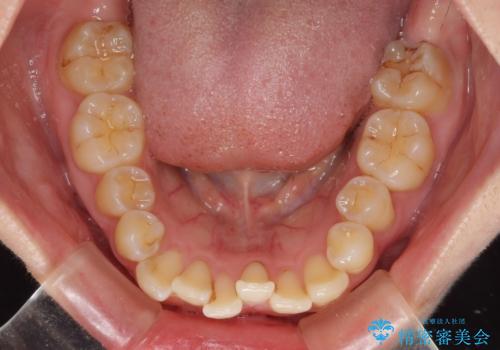

前歯のデコボコを解消 インビザラインによる矯正治療

- 上下前歯のデコボコと深い咬み合わせを気にして来院された患者様です。

インビザラインによる上下歯列の拡大と、IPR(歯と歯の間を削る)にるスペースの獲得により、前歯のデコボコを改善することとしました。

上の前歯をもう少し整えたかったのですが、患者様の治療を早く終了させたいという希望により、細かい叢生を残しての終了となりました。